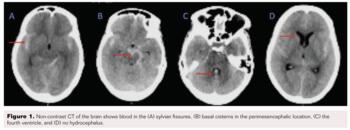

A 46-year-old woman presented with sudden onset headache associated with 2 to 3 episodes of vomiting and giddiness. On examination, her Glasgow Coma Scale (GCS) was 15/15 and power in all four limbs was 5/5. A non-contrast CT brain scan (Figure 1) revealed a diffuse SAH more predominant in the basal cisterns on the left side with intraventricular extension into the 4th ventricle (Fisher grade 4). There was no hydrocephalus. A CT angiogram (Figure 2) and diagnostic cerebral angiogram (Figure 3) demonstrated 3 intracerebral aneurysms in the following locations: inferior division of the right middle cerebral artery (MCA), 4.3 x 5 x 3.6 mm (AP x ML x CC); A1 segment of the left anterior cerebral artery (ACA), 2.1 x 2.2 x 1.4 mm; and basilar top, 11 x 8.1 x 8.3 mm with a neck measuring 6.8 mm. Based on the distribution of the SAH and morphology of the aneurysms, the basilar top aneurysm was assumed to be the cause of the SAH. Standard medical management included nimodipine, antiepileptics, antihypertensives, and analgesics.